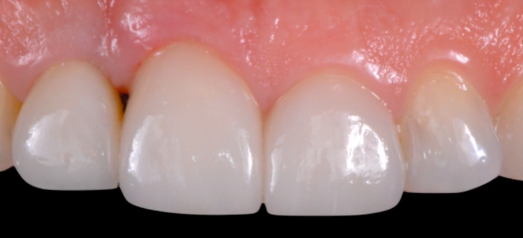

CLINICAL VIDEO Single Tooth Esthetic Implant Replacement - From Diagno

CAT# CV-080

Single Tooth Esthetic Implant Replacement - From Diagnosis to Surgery to Final Restoration

Dr. Francesco Mintrone

Dr. Sascha A. Jovanovic